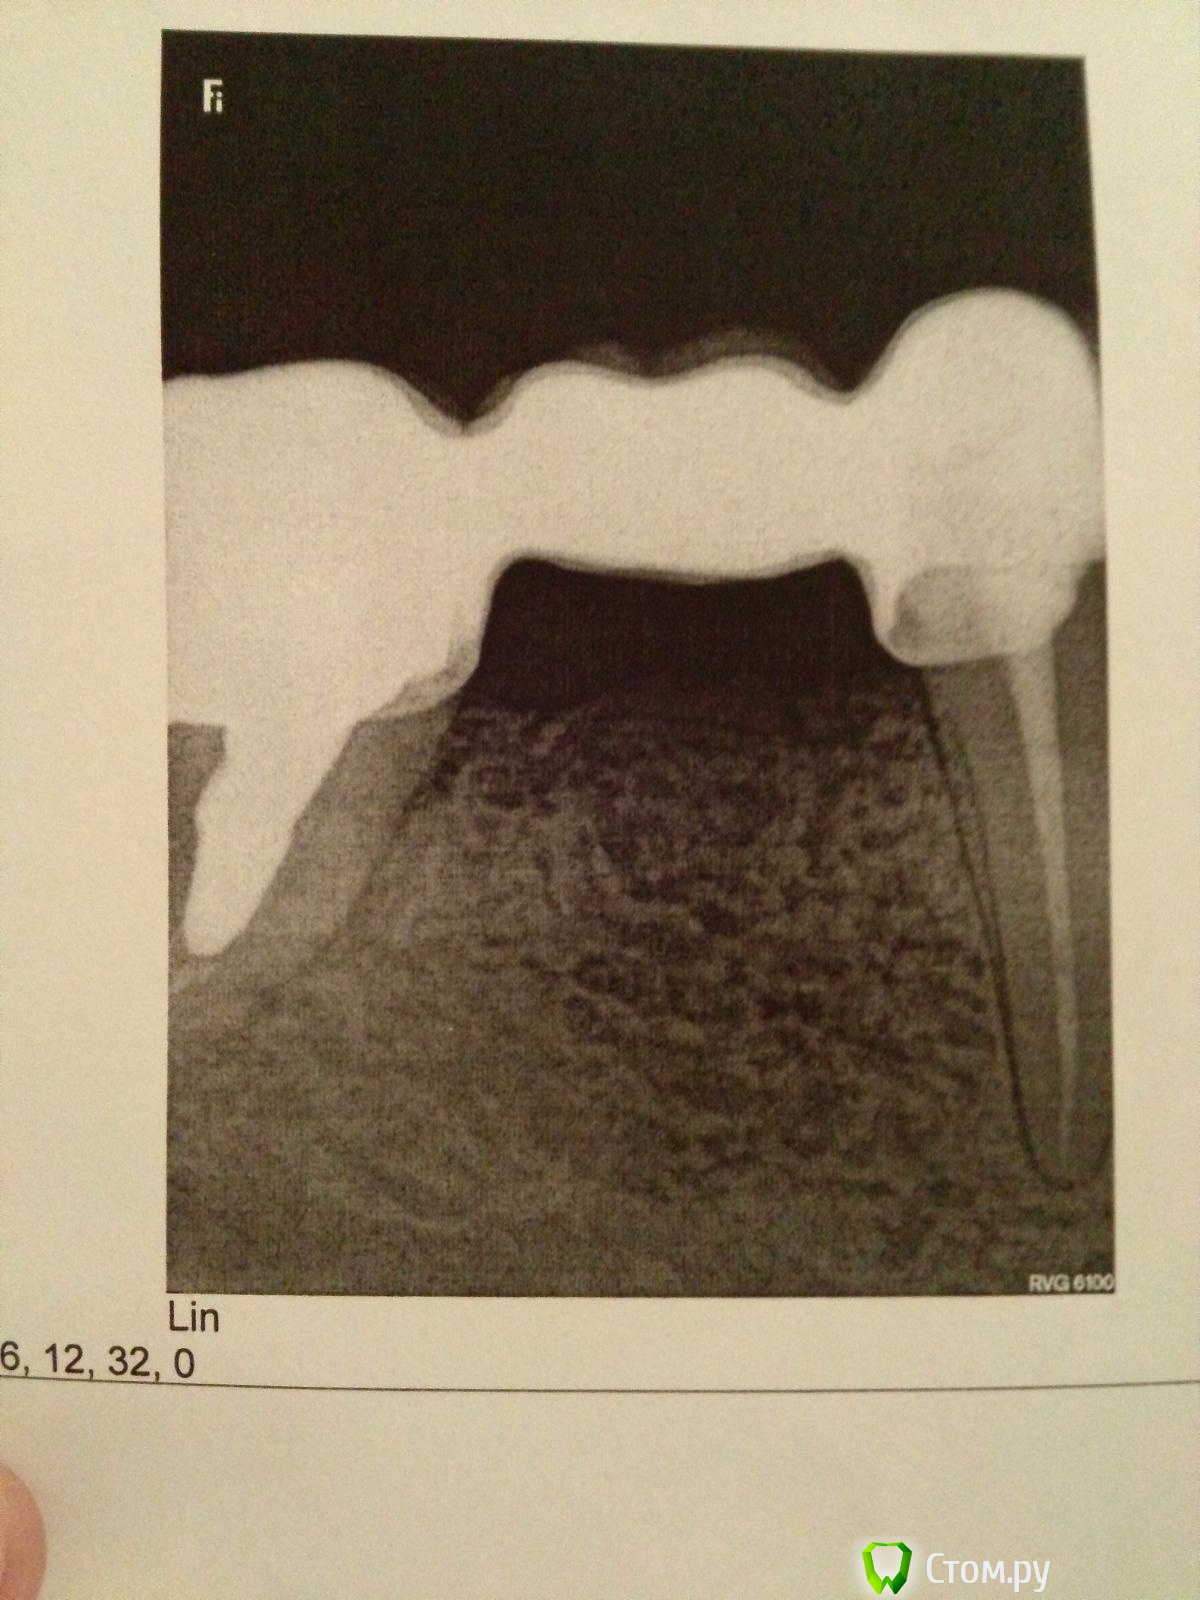

sabik Опубликовано 28 июня, 2014 Поделиться Опубликовано 28 июня, 2014 Здравствуйте! Ныл зуб долго, сходила в клинику, сделали 2 снимка, сказали периодонтит одного корня 6-ки, надо удалять зуб (((. Зуб под мостовидным протезом, 5-ки нет, мост на 4-ке и 6-ке, есть ли шансы сохранить такой зуб? При надавливании гной чуть вышел из под коронки. Снимок распечатали только один, не знаю видно зуб нормально или нет. Ссылка на комментарий

DokDent Опубликовано 28 июня, 2014 Поделиться Опубликовано 28 июня, 2014 Здравствуйте. Снимок неинформативен- 6-ка осталась за кадром 1 Ссылка на комментарий

red_butler Опубликовано 28 июня, 2014 Поделиться Опубликовано 28 июня, 2014 Снимок распечатали только один, не знаю видно зуб нормально или нет.Нет, зуб не видно Ссылка на комментарий

sabik Опубликовано 2 июля, 2014 Автор Поделиться Опубликовано 2 июля, 2014 Сходила сегодня, думала забрать второй снимок, оказалось, что у них только этот снимок в компьютере, получается перепутали, нужный удалили, расстроилась прям (((. Даже не знаю как быть теперь, опять что ли делать его? Может подскажите все-таки хоть примерно, обычно удаляют в практике зуб такой, в корне 6-ки вкладка, и вот на корне который видно на снимке, снизу и чуть вверх затемнение имелось, то есть периодонтит, как мне объяснили. И еще вопрос, можно ли мостовидный протез опять ставить, если не будет 5-ки, 6-ки, 7-ка живая имеется. Ссылка на комментарий